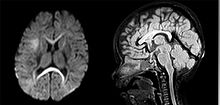

Parasagittal MRI of human head in patient with benign familial macrocephaly prior to brain injury (ANIMATED).gif

An MRI of a patient with benign familial macrocephaly (male with head circumference > 60 cm)